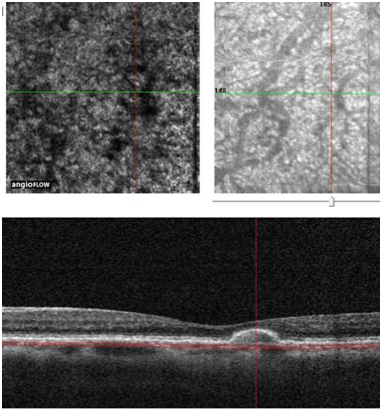

No abnormal «flow» signal is present, normal vessels are well individualized; choriocapillaris lobules are shown like clusters of half light signal. For now the best images we can obtain are 3X3 mm, possibly 6X6 mm and as a result of which the main use is centered on macula, and on ARMD In this case of subretinal new vessel which is a minimally classic choroidal new vessel7 (Figure 2) you can clearly see an abnormal flow signal pointed in red, followed by the OCT, confirmed by AF In one shot you diagnose a choroidal neovascularization and you replace AF and indocyanine green angiography (ICG). Angio OCT is also very contributive for retinal angiomatous proliferation (RAP), you can analyze your different layer and determine the course of the rap and nearly the complete morphology of the lesion. The analysis of the RAP could begin from the internal retina to the choroid In rap you observe at the retinal level, a deviation and dilation of retinal vessels in outer and medial retina (Figure 3) then you reach the anastomosis (Figure 4(1)) and the shape of the angiomatous lesion and nearly the total morphology of it (Figure 4(2,3)), the images are really better and more didactic than ICG and FA (Figure 5(1−3). The follow up of new vessels is also very interesting, with the confrontation of OCT you can easily highlight the activity of the new vessels (anastomosis, reflectance) and the regression of this activity after treatment (Figure 5−8) with sometimes very impressive images of «resting» new vessels (Figure 8,9) Angio OCT is also helpful to affirm the non vascular activity of a pigment epithelium detachment (Figure 10).

Figure 5 Three different approach of the rap. (1) Angio OCT. (2) FA. (3) ICG (red arrow on the RAP the scales of the images are different between Angio OCT and FA /ICG The evolution before (4) and after intravitreal ranibizumab (5).

Figure 6 Another RAP (1) before treatment (2) after treatment, intra vitreal ranibizumab (IVT).